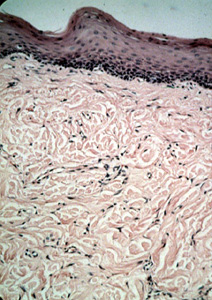

Esta microfotografía  ilustra  la fibrosis por irritación; generalmente es una lesión no encapsulada cubierta por el epitelio escamoso normal pero algo delgado. Incluso a esta resolución  puede ver el tejido fibroso bastante denso que se extiende por debajo del epitelio.

A mayor poder de resolución muestra que el colágeno ondulado es sumamente denso y con pocos fibroblastos. Hay poca o ninguna inflamación y el epitelio que cubren la superficie convexa está normal.